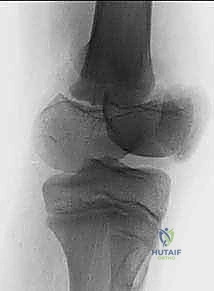

2. التصوير بالأشعة السينية (X-rays)

الخطوة الأساسية والأولى. يتم أخذ صور بأوضاع متعددة (أمامي خلفي، وجانبي، ومائل). في بعض الأحيان، قد يبدو الكسر غير مرئي بوضوح إذا لم تتحرك العظام من مكانها (Nondisplaced)، وهنا تبرز خبرة الطبيب في قراءة العلامات غير المباشرة مثل اتساع خط صفيحة النمو أو تورم الأنسجة العميقة.

تصنيف كسور صفيحة النمو: نظام سالتر-هاريس (Salter-Harris)

لغة التخاطب بين أطباء جراحة العظام حول العالم تعتمد على نظام تصنيف "سالتر-هاريس". هذا التصنيف لا يصف شكل الكسر فحسب، بل يرشد الأستاذ الدكتور محمد هطيف في تحديد استراتيجية العلاج الدقيقة وتوقع النتائج المستقبلية لنمو الطفل.

ينقسم هذا التصنيف إلى خمسة أنواع رئيسية، وسنشرحها هنا بالتفصيل المطبق على عظم الفخذ البعيد:

النوع الأول (Type I) والنوع الثاني (Type II): الكسور خارج المفصل

هذه كسور انفصالية تحدث خارج نطاق السطح المفصلي للركبة.

* النوع الأول (I): يمر الكسر أفقياً بالكامل عبر طبقة الخلايا المتضخمة في صفيحة النمو، مما يفصل المشاشة عن الكردوس دون كسر العظم نفسه. قد لا يظهر في الأشعة السينية بوضوح إذا لم يحدث انزياح.

* النوع الثاني (II): هو الأكثر شيوعاً. يمر الكسر عبر صفيحة النمو ثم ينحرف صعوداً ليكسر جزءاً مثلثاً من عظم الكردوس. هذه القطعة العظمية المثلثة تُعرف طبياً باسم "شظية ثورستون-هولاند" (Thurston-Holland fragment).

* التوقعات: على الرغم من أن هذه الأنواع عادة ما يكون لها تشخيص أفضل للنمو مقارنة بالأنواع الأخرى، إلا أن كسور الفخذ البعيدة تحديداً تكون أكثر عرضة لاضطرابات النمو (بنسبة تصل إلى 40%) مقارنة بإصابات صفيحة النمو في أماكن أخرى من الجسم (مثل المعصم)، وذلك بسبب الشكل المتموج المعقد للصفيحة الفخذية.